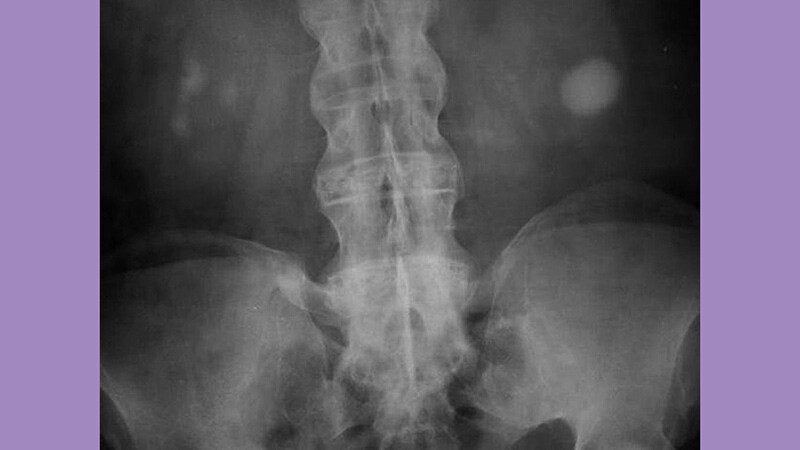

ACR 2020Tofacitinib Effective for Ankylosing Spondylitis in Phase 3 -